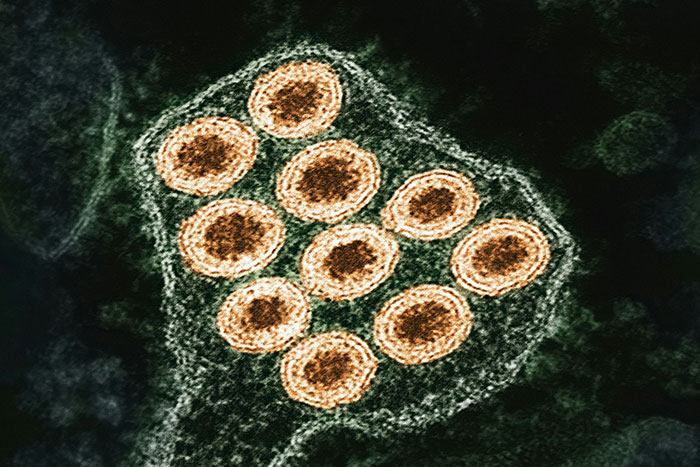

#17

Cold sores can cause inflammation of your brain. It’s called herpetic encephalitis and is likely to cause permanent brain damage even with treatment. It can also be caused by shingles, so getting the shingles vaccine is more important than you think.

Image credits: UnapologeticAberrant